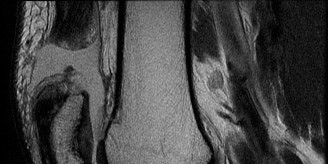

Given the patient's refractory symptoms at the three-month mark and the new onset of localized medial catching, advanced imaging via Magnetic Resonance Imaging (MRI) is indicated to evaluate the soft tissue structures and articular cartilage. MRI provides unparalleled visualization of the chondral surfaces, the medial patellofemoral ligament (MPFL), and the synovial plicae.

The axial T2-weighted fat-suppressed images reveal a thickened, fibrotic medial synovial plica extending from the medial capsule and impinging upon the medial femoral condyle during flexion. There is associated focal bone marrow edema in the medial patellar facet and the opposing medial femoral condyle, representing early chondromalacia patellae (Grade II chondral fissuring). The MPFL is intact with no signs of acute or chronic tearing. The tibial tubercle-trochlear groove (TT-TG) distance is measured at 14 mm, which is within the normal limits (<15 mm is normal, 15-20 mm is borderline, >20 mm is abnormal), suggesting that her maltracking is driven by soft tissue imbalance and dynamic kinetic chain deficits rather than static bony malalignment.